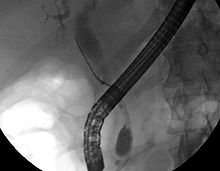

While abdominal imaging can be useful in the diagnosis of cholangiocarcinoma, direct imaging of the bile ducts is often necessary. Endoscopic retrograde cholangiopancreatography (ERCP), an endoscopic procedure performed by a gastroenterologist or specially trained surgeon, has been widely used for this purpose. Although ERCP is an invasive procedure with attendant risks, its advantages include the ability to obtain biopsies and to place stents or perform other interventions to relieve biliary obstruction.[12] Endoscopic ultrasound can also be performed at the time of ERCP and may increase the accuracy of the biopsy and yield information on lymph node invasion and operability.[54] As an alternative to ERCP, percutaneous transhepatic cholangiography (PTC) may be utilized. Magnetic resonance cholangiopancreatography (MRCP) is a non-invasive alternative to ERCP.[55][56][57] Some authors have suggested that MRCP should supplant ERCP in the diagnosis of biliary cancers, as it may more accurately define the tumor and avoids the risks of ERCP.[58][59][60]